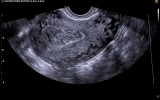

Фото: Эндометриоз на УЗИ

Эндометриоз на УЗИ

В ряде случаев проявления заболевания могут быть незаметными или пациентка может пренебрегать ими, считая их безобидными.